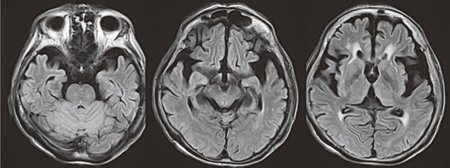

レビー小体型認知症(Dementia with Lewy Bodies:DLB)は、つい最近(1990年代後半)までは、その存在も知られていませんでした。横浜市立大名誉教授の小阪憲司医師による1976年以降の一連の報告で症状や病態が明らかになりました。

認知症患者の死後、脳組織をいろいろな染色液で染めてゆく研究過程で、大脳皮質や脳幹の神経細胞の中に「レビー小体」という物質が観察されました。そして、レビー小体型認知症の原因はα-サイヌクレイン(α-シヌクレイン)という蛋白でできている「レビー小体」であることが分かりました。

レビー小体型認知症の中核症状3項目は、認知症、幻視(具体的で、ありありとした)、パーキンソン症状です。これらの症状も階段状に進行しますが、症状は良くなったり悪くなったりといった具合に動揺し、短期的にみれば前進・後退がみられます。すなわち、日あるいは時間帯によって、症状の出方が違うという特徴もあるのです。

レビー小体型認知症の場合、認知機能障害が激しく変動し、幻視・錯視・誤認妄想は現実的で詳細な内容が繰り返して出現するとされています。パーキンソン症状のうち、3項目揃えば確診(DLB)、2項目で多分(probable DLB)、1項目では可能性(possible DLB)とされています。

初期に幻覚、幻視や錯視、妄想がでるのが特徴ですが、アルツハイマー型認知症と比べ近時記憶は比較的保たれます。幻視や錯視の出現率はアルツハイマー型認知症で30~40%、レビー小体型認知症で50~70%といわれています。